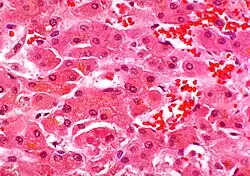

Mallorylichaampjes[1] (ook bekend als "alcoholische hyaline" of "Mallory's hyaline") (hyaline=glazig) zijn pathologische insluitsels in het cytoplasma van de lever cellen.[2] Ze zijn vernoemd naar Frank Burr Mallory. De cellen krijgen glazige insluitsels door secretiestoringen (uitscheidingsstoringen).

De lichaampjes zijn sterk eosinofiel en kleuren dus roze met een H&E-kleuring. De lichaampjes zelf bestaan uit intermediaire keratinefilamentproteïnen ontstaan bij de door ubiquitine gereguleerde afbraak van proteïnen of gebonden door andere proteïnen zoals hitteschokproteïnen en nucleoporine 62.